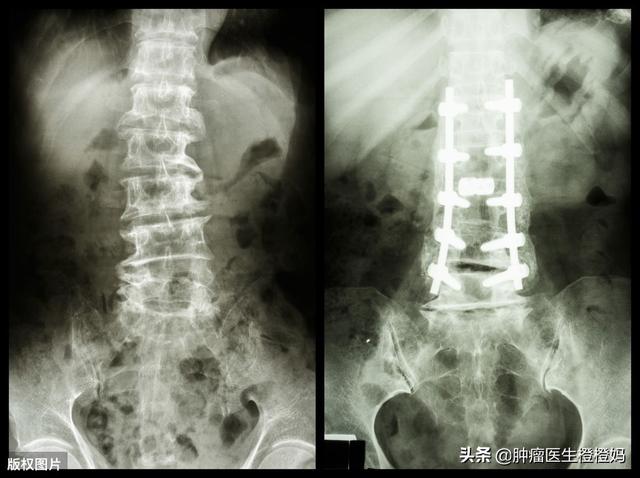

Cette fois, Hai et mon fils m'ont transportée à l'hôpital du cancer, malgré mes objections. Un scanner a révélé que les métastases osseuses avaient provoqué une fracture des vertèbres lombaires. Sur les conseils du médecin, je n'ai pas eu d'autre choix que de commencer une radiothérapie. Chaque jour, mon fils me poussait en fauteuil roulant jusqu'à la salle de radiothérapie et me portait jusqu'à l'appareil de radiothérapie. En raison de l'intolérance de mon corps, j'ai dû subir 20 traitements au total, qui ont duré près de deux mois.

- En cas de fracture, il est temps d'obtenir l'aide d'un chirurgien orthopédique et, selon la situation, il peut être nécessaire de procéder à une fixation fémorale, à un remplissage de ciment vertébral, etc. EtIl est important d'éviter tout mouvement au niveau du site de la fracture afin de ne pas aggraver la blessure.